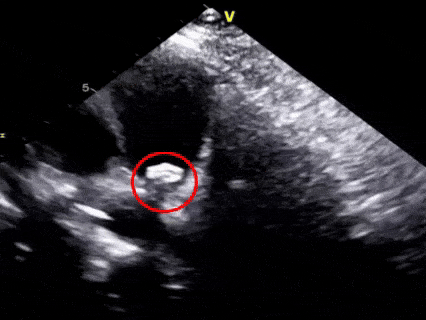

二“扣”,双盘扣合

超声下可见右盘面展开后盘面骑跨在肺动脉与主动脉两侧